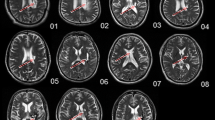

In this study, the aIPS also played a significant role. The interhemispheric connections between the bilateral aIPS and M1 or S1 were correlated with residual function. The bilateral aIPS was additionally analyzed using a seed-based approach to investigate unobserved connections related to residual motor function. The aIPS was mostly connected with the parietal and occipital lobes, and around the central sulcus. Figure 2 is the t-map (uncorrected p < 0.001) constructed by analyzing the correlation between the results from our seed-based approach and motor function scores. Only interhemispheric connections connected with M1 and S1 (ipsilesional aIPS-contralesional M1, peak MNI coordinates [30, − 12, 52], t = 4.46; contralesional aIPS-ipsilesional M1, peak MNI coordinates [− 34, − 10, 54], t = 5.35; contralesional aIPS-ipsilesional S1, peak MNI coordinates [− 40, − 22, 52], t = 5.35) were observed. We verified that the interhemispheric connections between the bilateral aIPS and the primary sensorimotor regions played an important role in motor function.

The regions connected with a the contralesional aIPS and b the ipsilesional aIPS are related to motor function. The regions indicate significant connections correlated with residual motor function among all connections of the aIPS in the whole brain. The t-maps (p < 0.001) are axial views (MNI coordinate, z = 52). Interhemispheric connections between primary sensorimotor regions and the aIPS were correlated with residual motor function. IL ipsilesional side, CL contralesional side